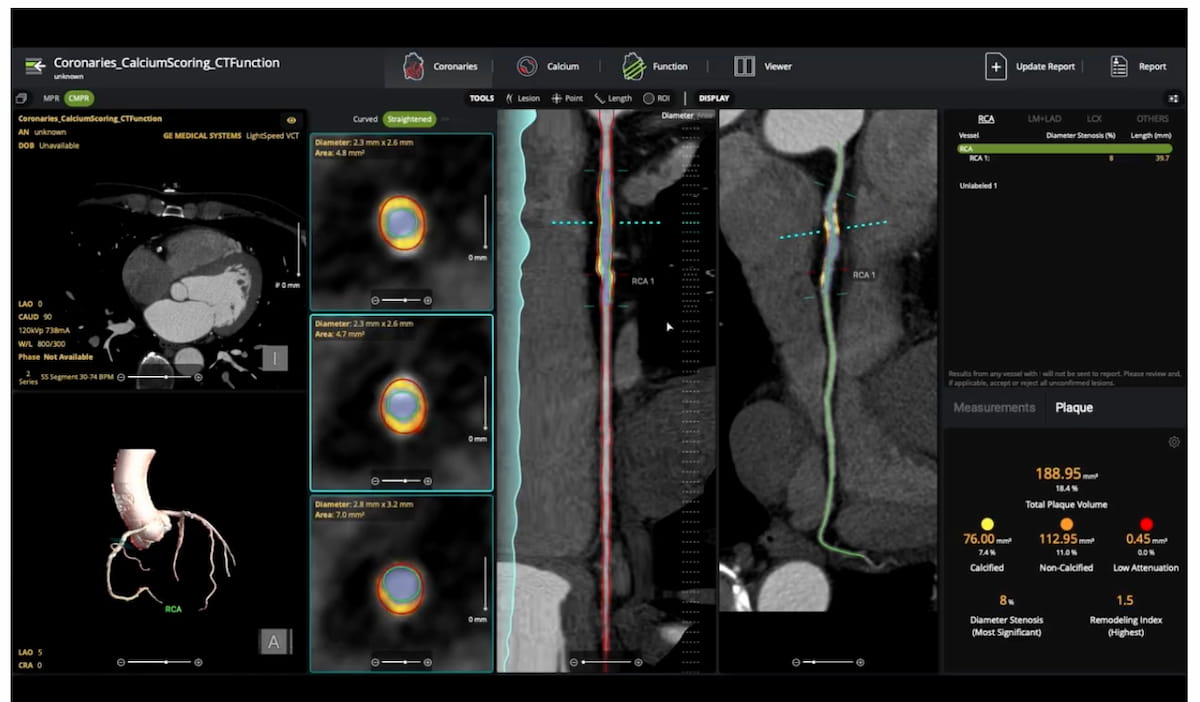

The updated Heartflow Plaque Analysis software reportedly offers enhanced 3D visualization of plaque type, volume and distribution based on coronary computed tomography angiography (CCTA) imaging.

Use of the AI-powered Salix Coronary Plaque module, which offers detection of high-risk plaque within 10 minutes based off of CCTA scans, will reportedly qualify for $950 in Category 1 CPT reimbursement in 2026.